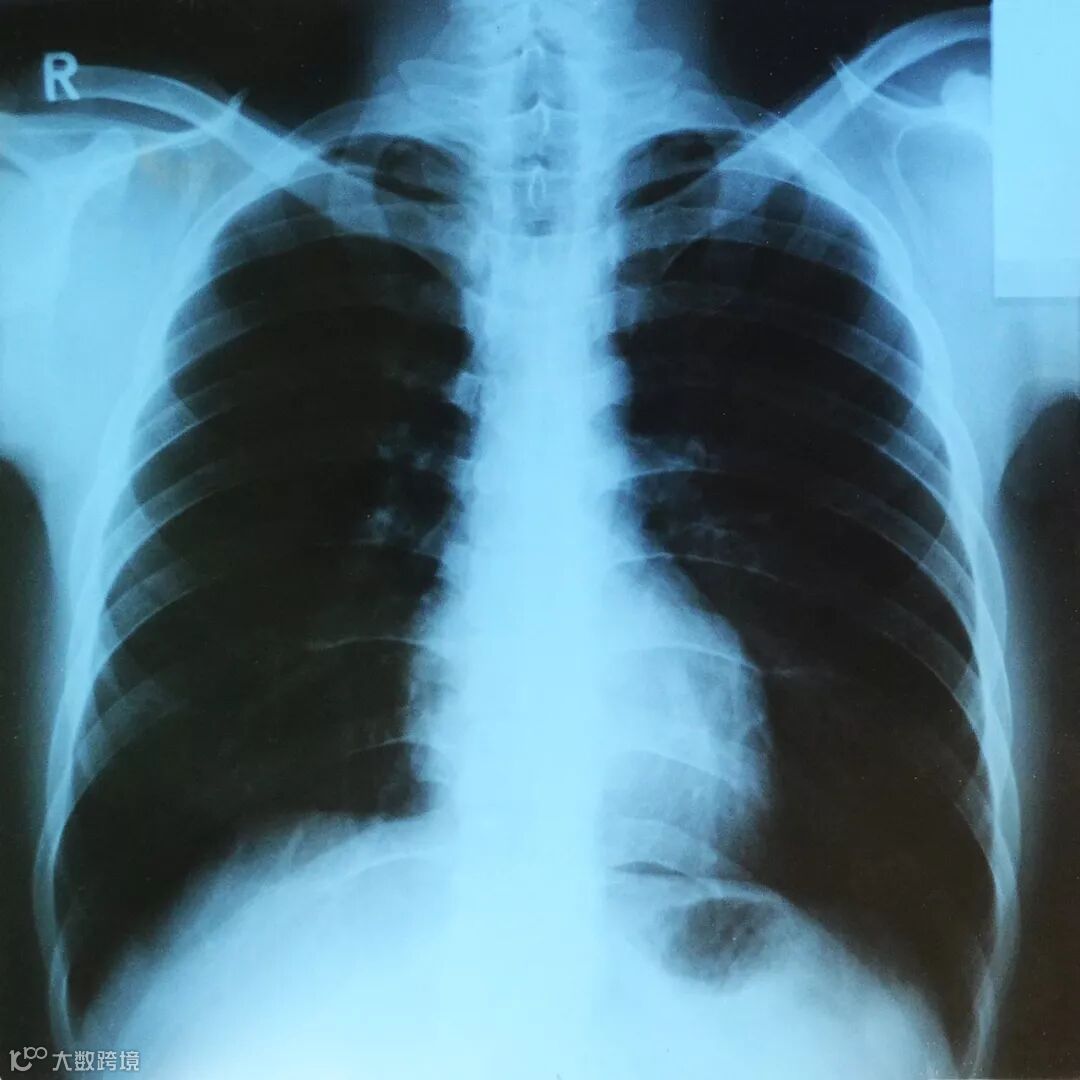

由于锁骨位于人体的最前方,所以拍X射线胸片时不会被其他骨骼或肌肉遮挡,可以清晰地看到它的轮廓。

因此,发现失踪者遗骨时,如果能够与其生前拍摄的X射线胸部照片进行对比,就能够通过锁骨鉴定身份。